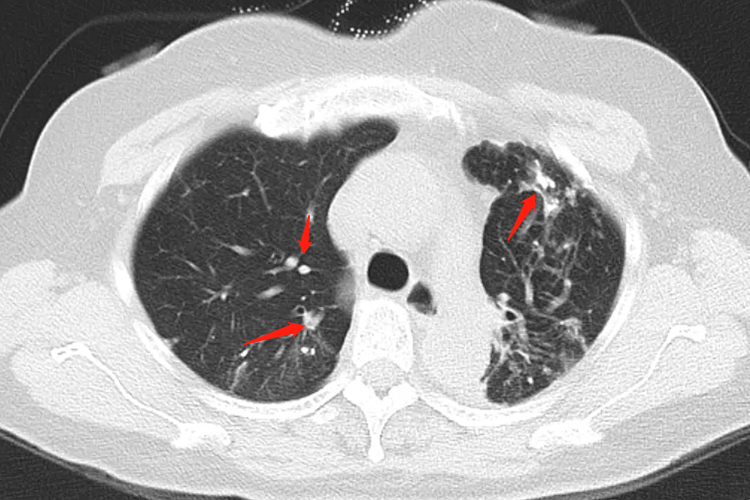

肺结核干酪样坏死在影像表现为病变部位出现均匀或不均匀中等密度的大片状实变影,早期类似大叶性肺炎,CT平扫密度较普通肺炎密度高,在大片实变影中可出现单个无壁空洞或多个蜂窝状的无壁小空洞,空洞多为虫蚀样;增强扫描病灶可有强化;在同侧或对侧肺可见支气管播散病灶。